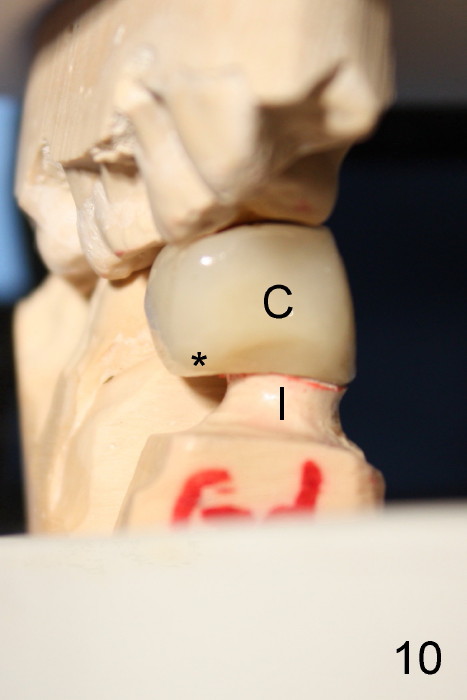

五十多岁的吴先生右下六有根分叉感染(图一),有一次到外地出差疼痛难忍拔除了,一两年后才同意植牙,图二显示已经愈合近远中(M, D)牙槽窝,六乘十七毫米植牙(图三I)好像种得很端正,其实并不完全是这样。让我们回到图二,沿着虚线做个冠状切面,显示右上六号牙以及右下六牙槽骨(图四*),与对侧六号牙冠状切面(图五)对比,右下六牙槽骨往舌侧(L)倾斜(B:颊侧),要植入长而宽的植牙,它就往舌侧倾斜(图八)。为了与对侧牙齿咬合,必须用二十度倾斜的基牙(图六A),但是临床上通过基牙而改变的角度还不够(图七),所以最后牙冠(图十C)不在植牙(I)长轴上,也就是一部分牙冠是悬臂的(*),容易造成陶瓷断裂,基牙松动。避免悬臂牙冠最好的方法便是拔牙后即刻植牙(图九),如果骨质已经吸收,植骨(图十一红色)或者骨扩张时尽量让颊侧骨板往颊侧移动,纠正植牙倾斜角度。